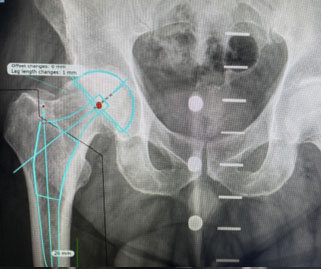

Ejemplo propio Prótesis Total de Cadera

Preparación y Calibración

de la cirugía

Resultado: Prótesis

Total de Cadera D